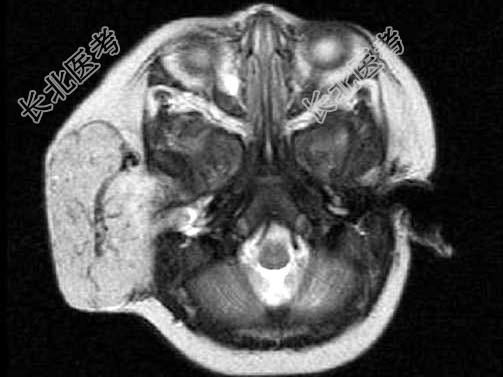

- 单项选择题老年患者,右侧面部肿胀, 呈青紫色,MRI检查如图所示, 最可能的诊断是 ( )